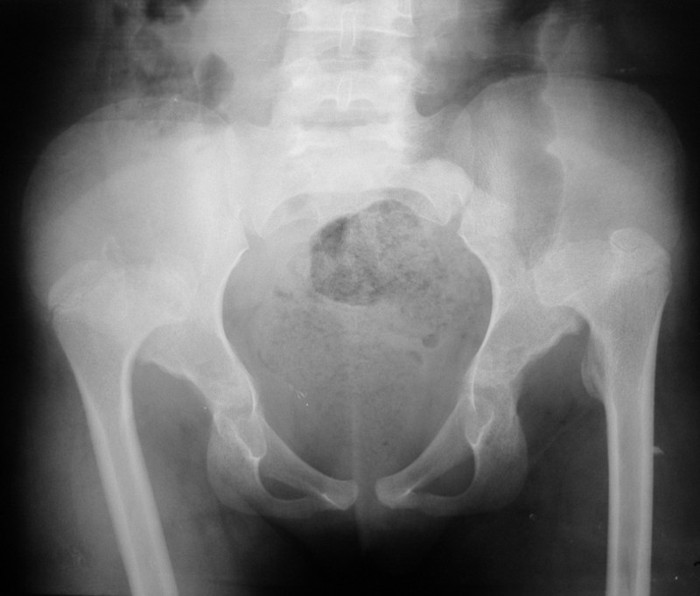

На рентгенограммах от 14.10.10. таза отмечается вывих обеих бедренных костей кверху с образованием неоартрозов на уровне крыш подвздошных костей. Вертлужные впадины мелкие, запустевшие. Крыши скошены. Головки бедренных костей грибовидной формы, шейки укорочены, широкие – врожденный вывих обеих бедер.